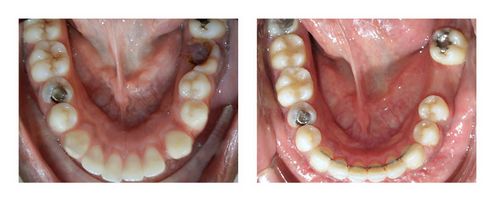

Cas Orthodontie Paris 8 : Absence d’une molaire inférieure, décalage des arcades et expulsions de canine

La situation de départ était alarmante : absence d’une molaire inférieure (deuxième molaire inférieure en place de la première à droite), anomalie de forme de la deuxième prémolaire inférieure droite, décalage entre les arcades d’une dent (7 à 8 mm) à droite lié à la forte asymétrie de l’arcade inférieure, expulsion des canines supérieures vers l’extérieur, incisives latérales supérieures reculées.

La forme et le volume de la prémolaire très perturbée et le déficit de place ont amené à poser l’indication d’extractions de prémolaire. La place créée par ces extractions a permis d’aligner les dents antérieures et de faciliter la correction du décalage des arcades. La difficulté a été d’avancer la deuxième molaire inférieure droite de 8 mm. Cette avancée s’est faite sous l’effet d’élastiques inter-arcades, mais une minivis aurait pu aussi être utilisée. Grâce à ce déplacement, la dent de sagesse inférieure droite a pu se positionner correctement sur l’arcade et donc permettre d’éviter un implant. La durée globale de traitement a été de 2,5 ans.